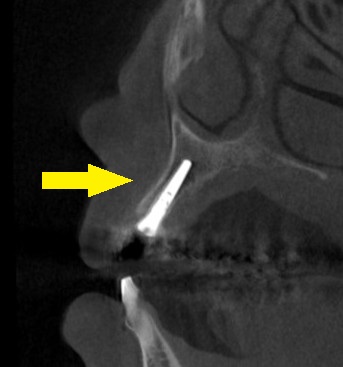

レントゲン写真、CTを撮影してみると、周囲の骨の状態は良好でしたので、この場合は、抜歯即時インプラント埋入をお勧めしました。

下の写真下段が手術前後のCTです。